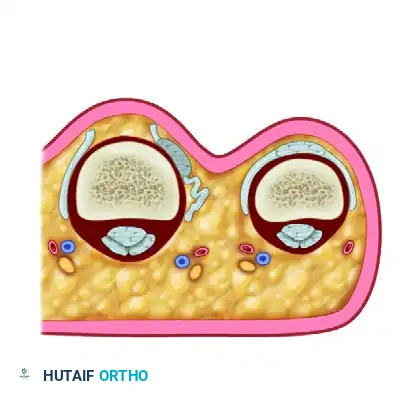

Irreducible dislocation of the proximal interphalangeal joint. The collateral ligament has been torn, and the lateral band of the extensor hood is trapped within the joint (Dorsal view).

Lateral view demonstrating the trapped lateral band preventing concentric reduction.